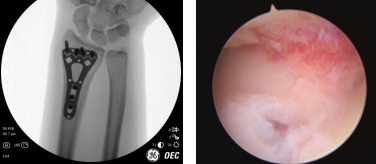

“我是一个耐痛力挺强的人,摔伤后我真觉得左手腕疼得受不了”,术前检查显示其左桡骨远端骨折。当天,齐伟亚主任手术团队为杨女士进行了“关节镜辅助下左桡骨骨折复位内固定术”,术中,手术团队在关节镜下观察手腕内部的情况,将碎裂的关节面拼接、复位和内固定。手术切口很小,不到2cm,还做了美容缝合。齐主任做完手术后没有进行石膏固定,关节镜微创病房都备有早期康复器材,患者术后第二天就可以在医师指导下进行早期康复锻炼。

术前

术中

术后即刻(左图)微创小切口(右图)